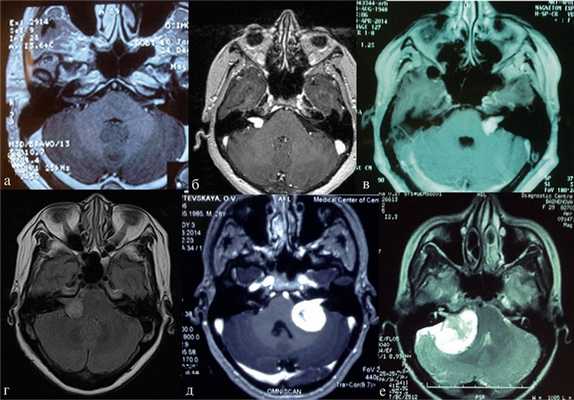

В практической деятельности наиболее универсальными являются классификации, предложенные Koos [11] и Samii [12]. Они основаны на оценке размеров невриномы и ее отношении к окружающим мозговым и костным структурам (рис. 1, 2).

Рис. 1.Иллюстрация классификации неврином слухового нерва по Koos. а — I стадия — опухоль находится в пределах внутреннего слухового прохода, диаметр экстраканальной части составляет 1—10 мм; б — II стадия — опухоль вызывает расширение канала внутреннего слухового прохода и выходит в мостомозжечковый угол, ее диаметр составляет, 11—20 мм; в — III стадия — опухоль распространяется до ствола головного мозга без его компрессии, диаметр составляет 21—30 мм; г — IV стадия — опухоль вызывает компрессию ствола головного мозга, ее диаметр более 30 мм.

Рис. 2.Классификация неврином слухового нерва по M. Samii. а — Т1 — интрамеатальная опухоль (рис. 2, a); б —Т2 — интра-экстрамеатальная опухоль; в — Т3а — опухоль заполняет мостомозжечковую цистерну; г —Т3b — опухоль распространяется до ствола головного мозга; д —Т4а — опухоль вызывает компрессию ствола; е —Т4b — опухоль грубо деформирует ствол мозга и IV желудочек.

В клинической практике обе эти классификации следует равноценно рассматривать в качестве основных принципов оценки клинической стадии заболевания (опция).